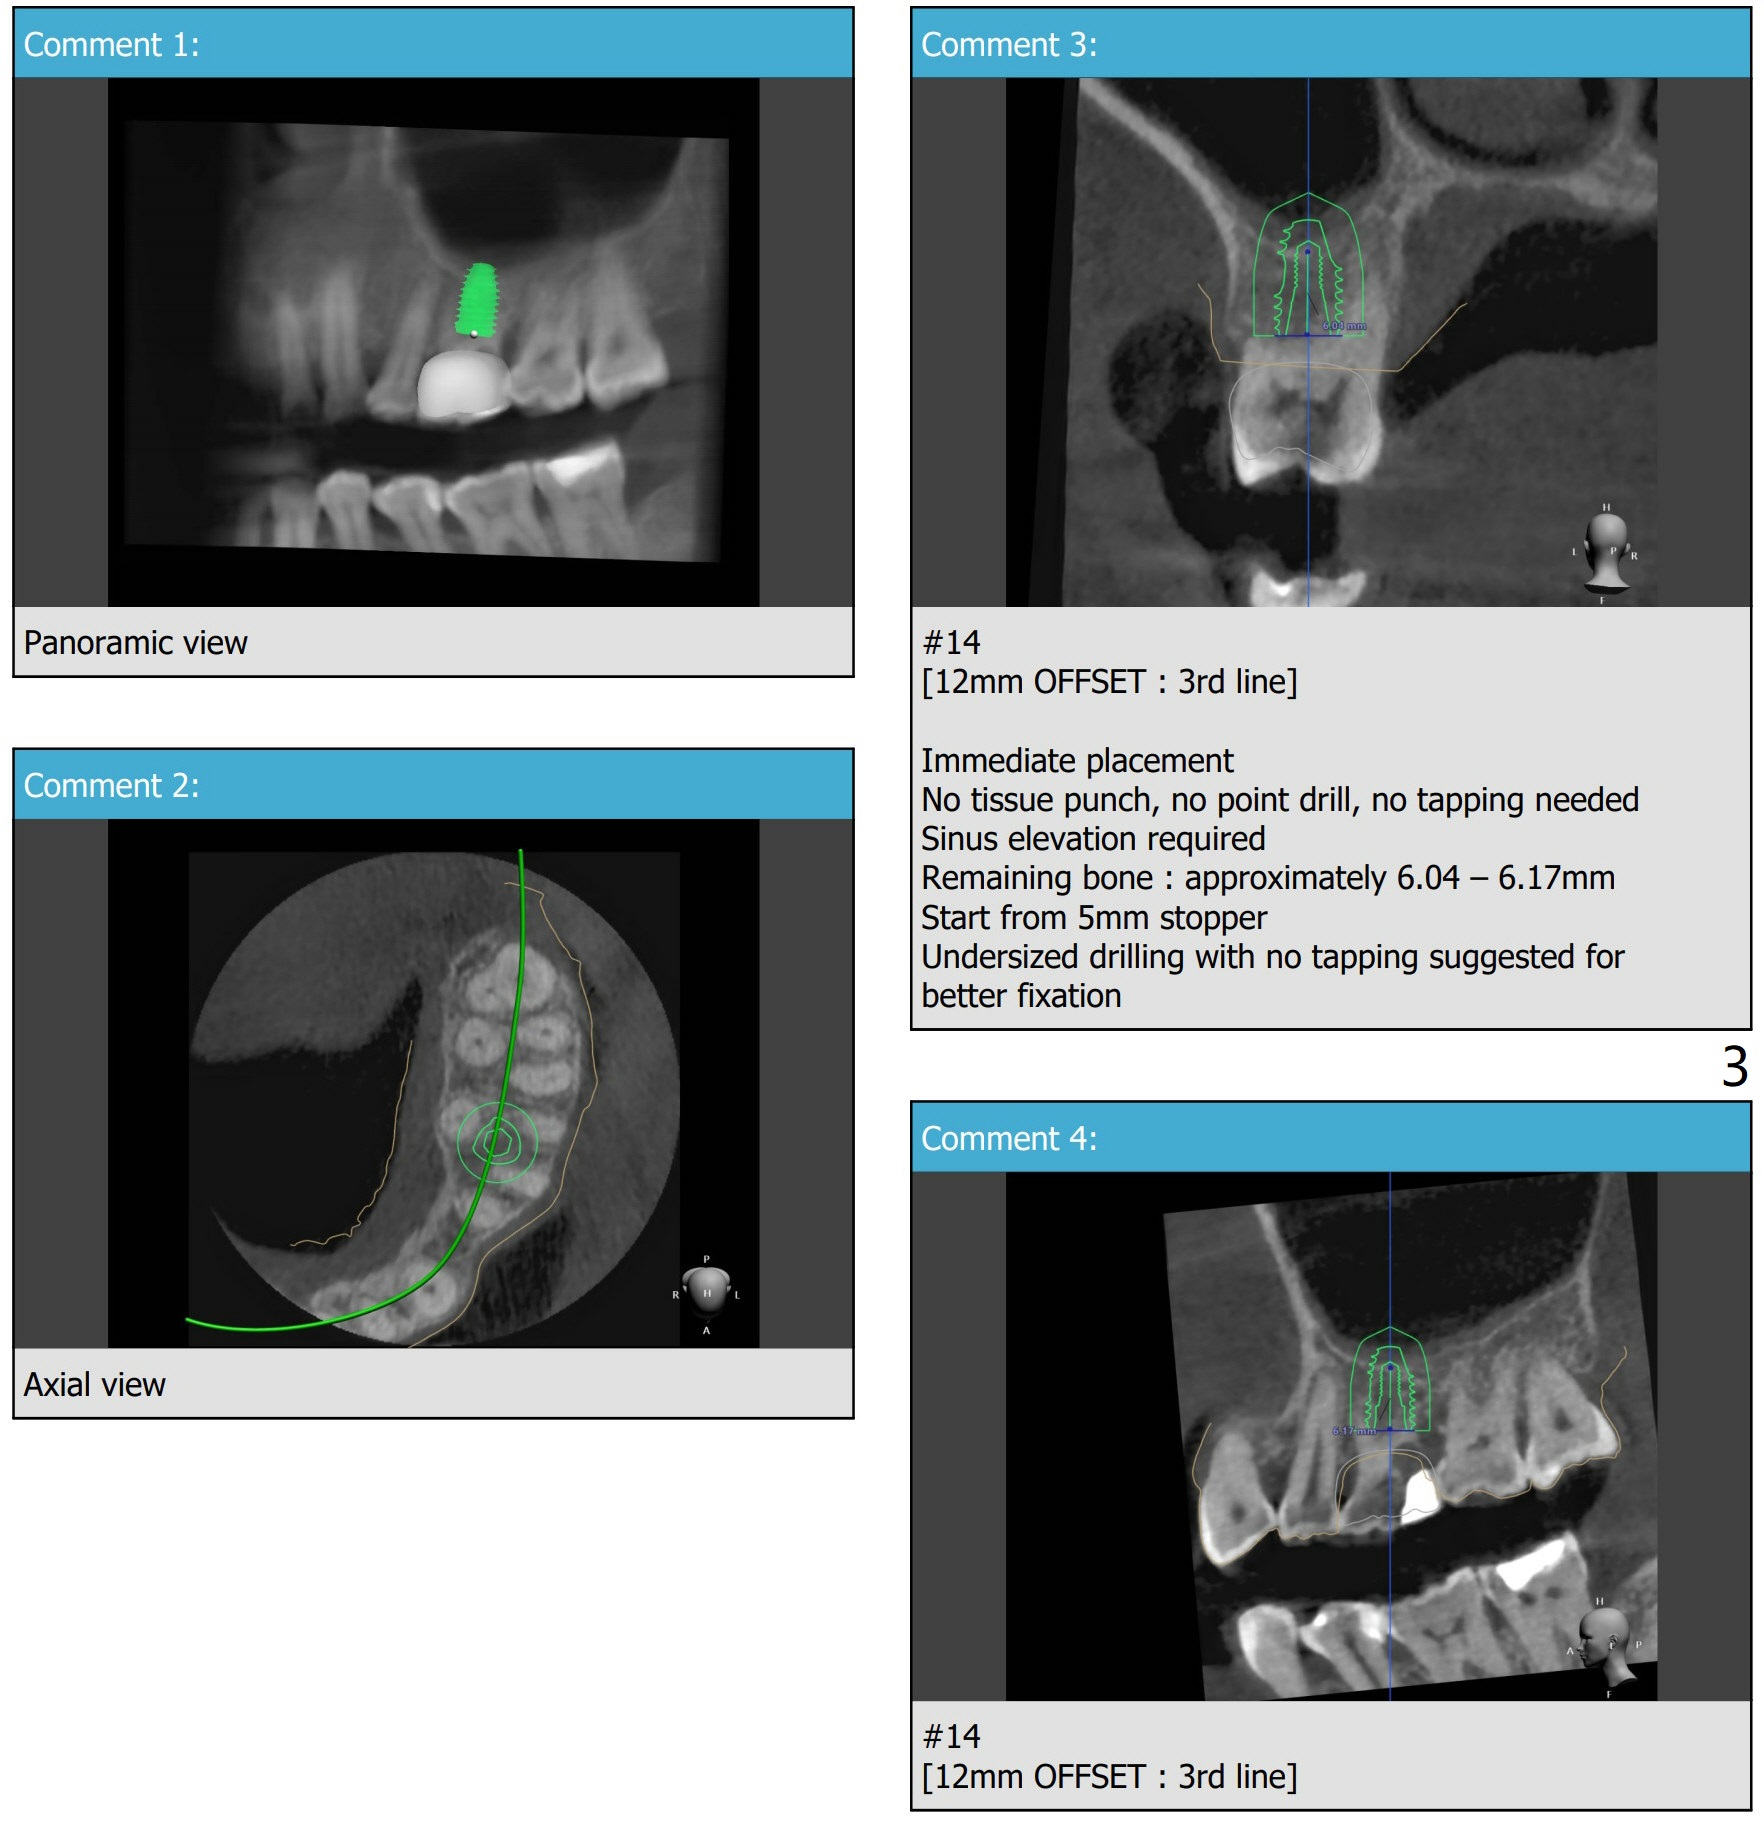

即刻种植与提升

粘性骨粉